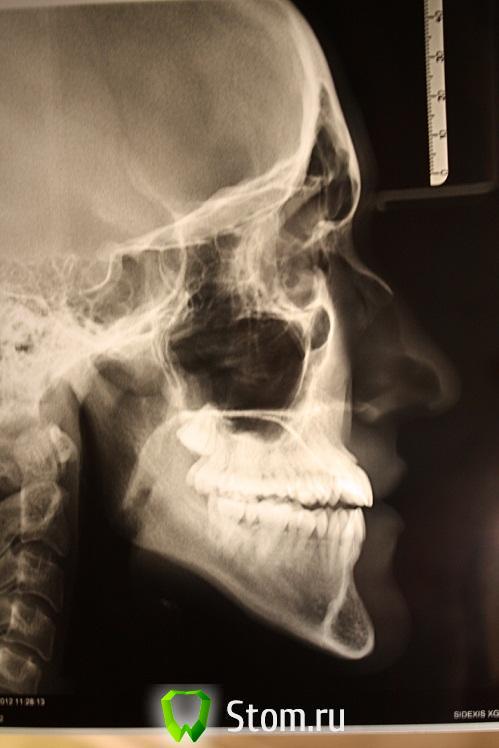

в 11 лет нам пришлось обратиться к ортодонту.причина 1-прямой прикус,2-на верху отсутствуют клыки.Лечение одели пластины и ждали выхода клыков.В это время происходит смена молочных на постоянные зубы,но клыки не выходят.врач отменяет пластинки.одевает брекеты.Удаляет два зуба -четверки нижняя челюсть.на верхней открывает клыки и брекетами ставит на место.Исправление прикуса продолжалось до 16 лет.В 16 положительный результат был достигнут в полной мере.Прикус правильный,клыки на месте,зубы ровные.сняли брекеты и мы пошли домой.В 18 лет опять пришлось обращаться к ортодонту.на верху зубы стали в разные стороны поворачиваться.врач сказала ,что она сделала все что смогла.А повторно одевать брекеты нельзя.мы поняли что лечение закончилось. В 21 год у дочери произошло опущение -десны/фото/

Проходит пол-года,винт раздвинул зубы по максимуму,в результате зубы приняли правильное положение,,а опущенная десна не восстановилась,и добавилась еще одна проблема-нет смыкания зубов вообще.Смыкаются только 6 7 верха с 6 низа с одной стороны.Снимки прилагаются,.Что делать,доктор?